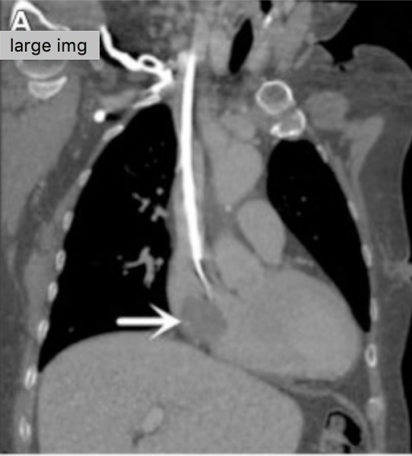

![]() Catheter-related atrial thrombus. Yang et al., JVS, 2018. | Frequently asymptomatic, incidental finding on imaging (95-99% of cases) | Systemic anticoagulation with warfarin or novel anticoagulant as for treatment of DVT Catheter removal or exchange (Figure 2) |

Table 1. Non-infectious hemodialysis contraindications and their suggested management.